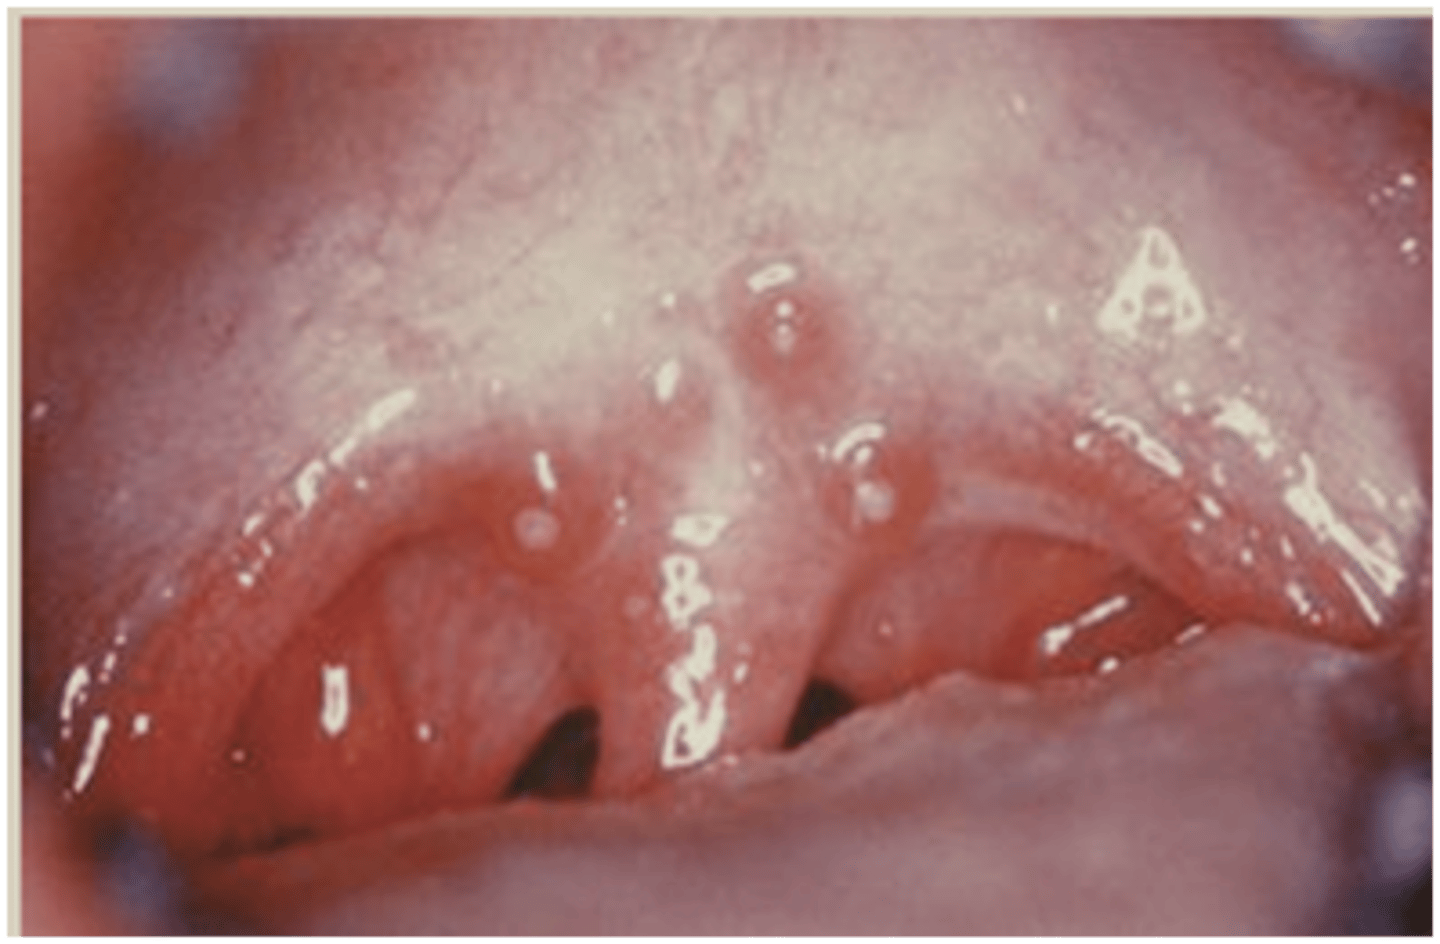

What is nicotinic stomatitis? (+ common location)

round white lesion + small red dot in center (inflamed salivary gland)

⢠pipe/cigar use

⢠common location: hard palate